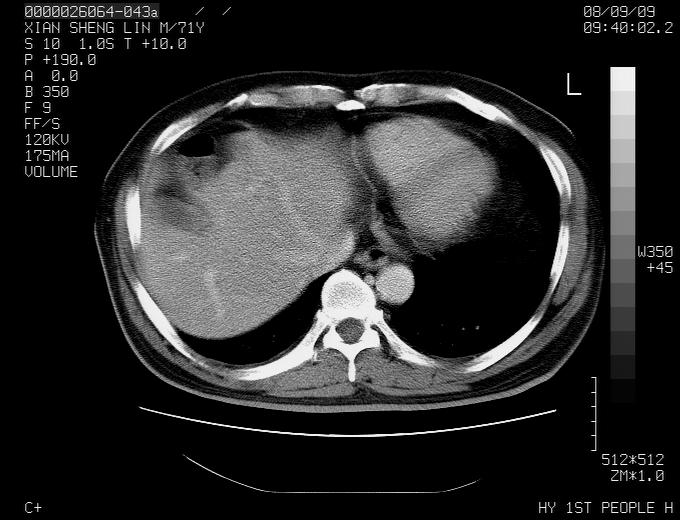

患者,男性,71岁,因咳嗽而就诊,

1,右肺中心型ca,气管隆突旁淋巴结转移。

2,右膈明显抬高,建议肝脏扫描排除转移或原发灶。